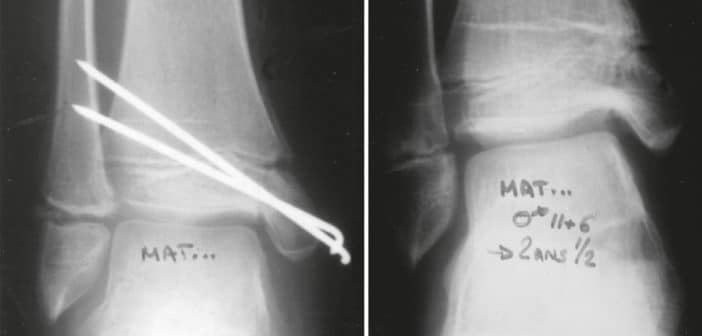

- Les fractures qui nécessitent un abord chirurgical